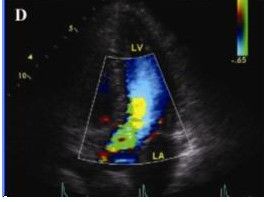

2.肥厚型心肌病可見不對稱性室間隔肥厚,室間隔厚度與左室後壁厚度之比大於1.3:1;二尖瓣前葉收縮期前移;左心室腔縮小,流出道狹窄;左心室舒張功能障礙,包括順應性降低,快速充盈時間延長,等容時間延長等。

原發性心肌病 2.肥厚型心肌病:常見體徵有心濁音界向左擴大、心尖搏動向左下移位,可見抬舉性衝動或心尖雙搏動;胸骨左緣下段心尖內側可聽到收縮中期或晚期噴射性雜音,向心尖部傳播,可伴有收縮期震顫,見於有左心室流出道梗阻的患者。凡增加心肌收縮力或減輕心臟負荷的措施(如給予洋地黃類、異丙腎上腺素、亞硝酸異戊酯、硝酸甘油、做Valsalva動作、體力勞動後或早搏後)均可使雜音增強;凡減弱心肌收縮力或增加心臟負荷的措施(如給予血管收縮藥、β受體阻滯劑、下蹲、緊握拳等)均可使雜音減弱,約半數患者同時可聞及二尖瓣關閉不全的雜音;第二心音可呈反常分裂,呼氣時明顯(由於左心室噴血受阻,主動脈瓣延遲關閉所致)。心律失常以心房纖顫為多。非梗阻肥厚型心肌病僅心臟輕度增大,肺動脈瓣第二音分裂,無反常的逆分裂,雜音較少且較輕。